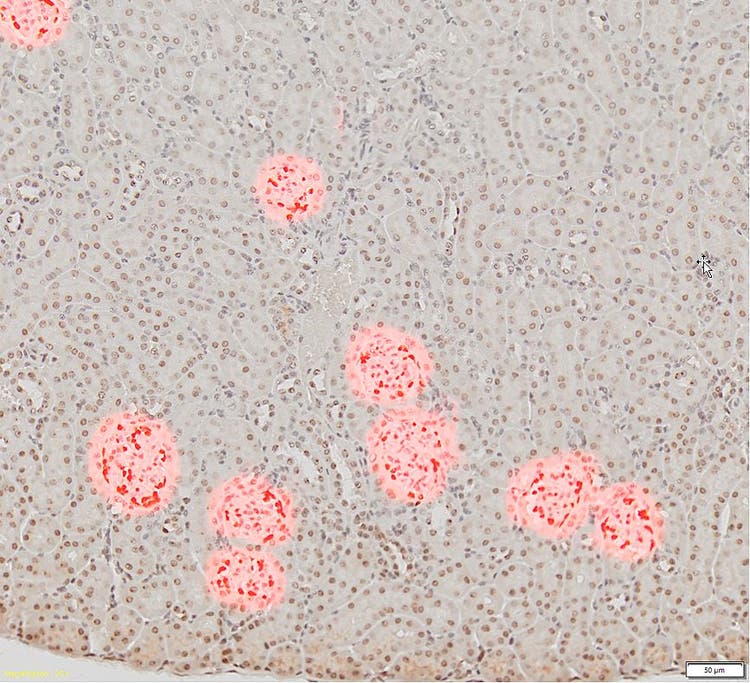

[Izq.] Portaobjetos con corte de tejido renal en 20x que muestra glomérulos teñidos de marrón oscuro. [Dcha.] Portaobjetos en 10x que muestra la detección basada en el método de valor umbral convencional (en rojo) y en donde no se distinguen las células glomerulares de las otras células tisulares.

Por lo general, para analizar estas estructuras en imágenes digitalizadas, los investigadores seleccionan los glomérulos de forma manual; pero, hay que dedicar mucho tiempo. Por otro lado, los métodos tradicionales de segmentación automática, como los algoritmos basados en umbrales, no llegan a identificarlos, tal y como se mencionó anteriormente.